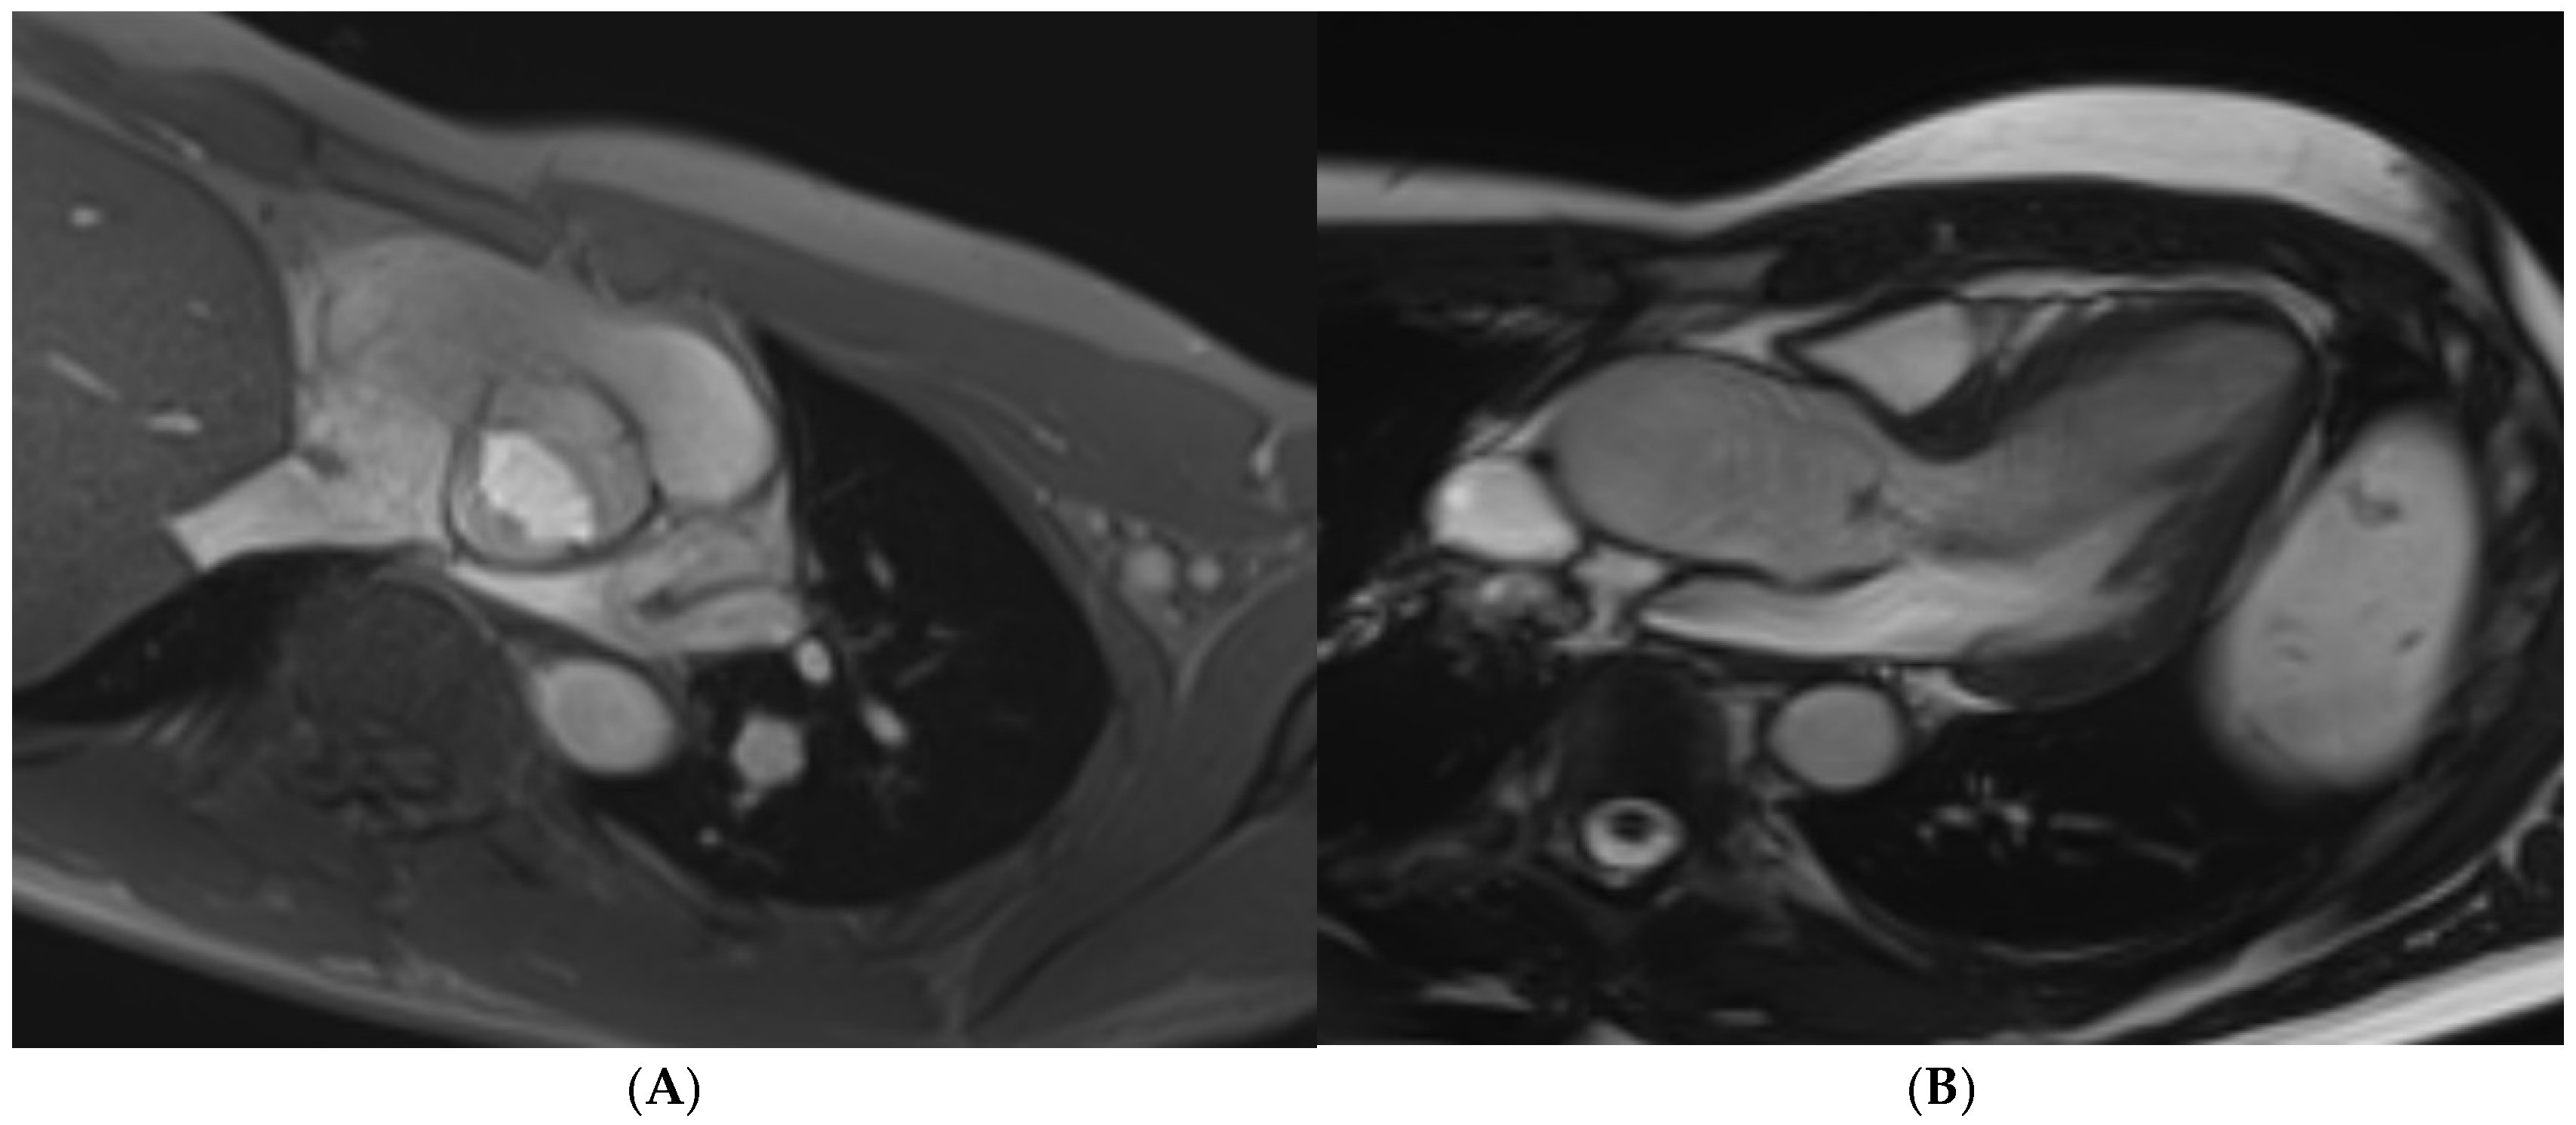

12. Mitral Valve Prolapse